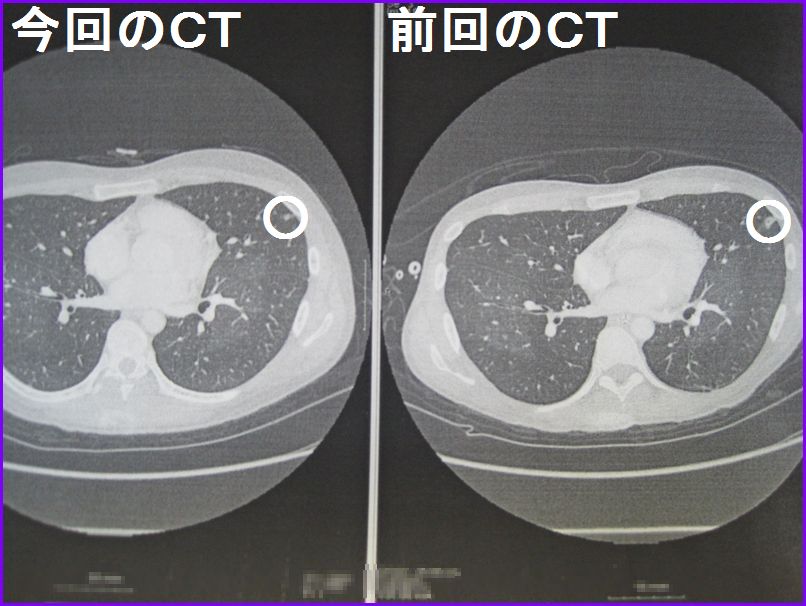

9日(月)に撮ったCTは・・・・

放射線科の正式なコメントはまだですが、主治医の先生の見解では

「骨盤内の腫瘍も小さくなっているし、肺に写っていた白い影も縮小している」

<肺のCT画像>

○の付いた部分が肺転移が疑われている白い影です。

前回撮影したCT画像より今回は縮小しているように見えます。

まだ何なのか確定しているわけではないので気持ち悪いですが、でかくなっているわけではないので一安心といったところです。